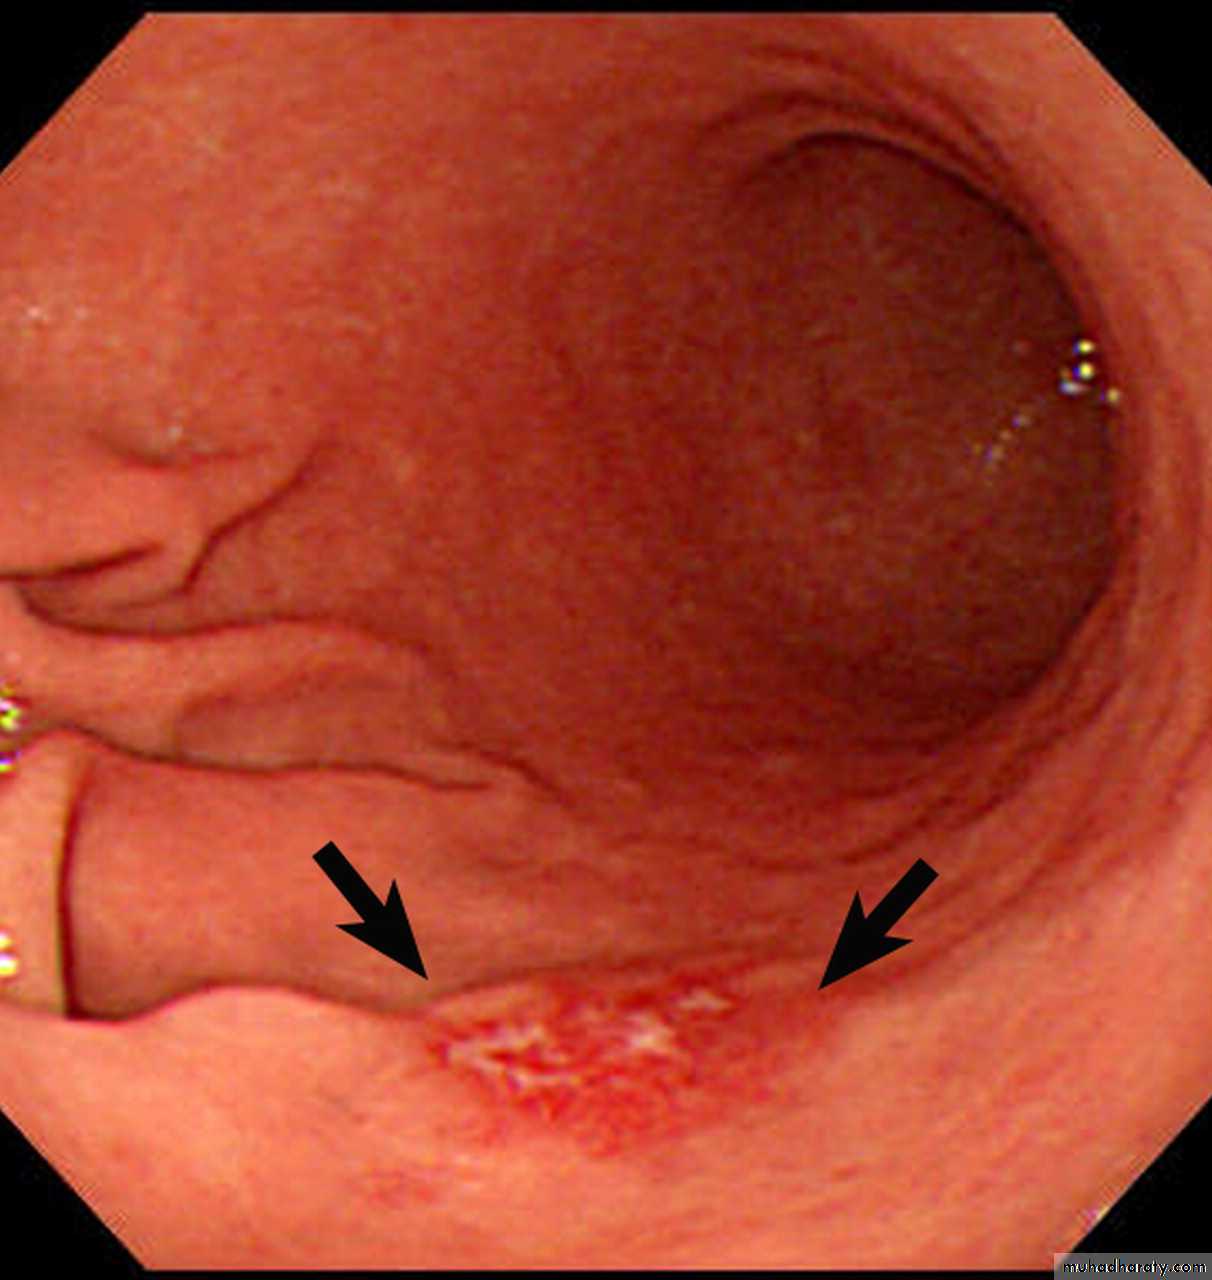

Krukenberg tumors: Bilateral ovarian tumors (arrows). These represent ovarian metastases from a gastric adenocarcinoma.

Low-grade gastric MALT lymphoma with diffuse mucosal nodularity in a 60-year-old woman. photograph of the resected specimen shows diffuse nodularities (arrows) in the gastric antrum.